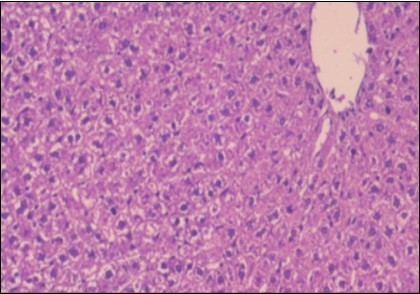

The histological examination of the livers of control rats feeding standard diet showed normal architecture hepatocytes, blood sinusoid and central vein, figure 6. The rats which were fed on a (HFD), showed swollen hepatocytes with vacuolated cytoplasm filled with fatty infiltration, congested central vein and disappearance of blood sinusoids, figure 7. By comparison, the liver of rats that were treated by fennel after obesity and control mice observed nearly normal of the hepatocytes with eosinophilic cytoplasm, central vein and clear blood sinusoids and more bi-nucleated cells, figure 8. While examination of rats' liver that were treated by Ator and after the obesity appears, they showed mild fatty change in hepatocytes, few hepatocytes retain is eosinophilic cytoplasm and central vein figure 9. Liver of rats that were treated by fennel and Ator after obesity and control rats are showing nearly normal hepatocytes figure 10.

Figure 9.Photomicrogragh of liver section of treated rat with Ator drug showing mild fatty change in hepatocytes, few hepatocytes retain is eosinophilic cytoplasm and central vein , (H&E) (40X).